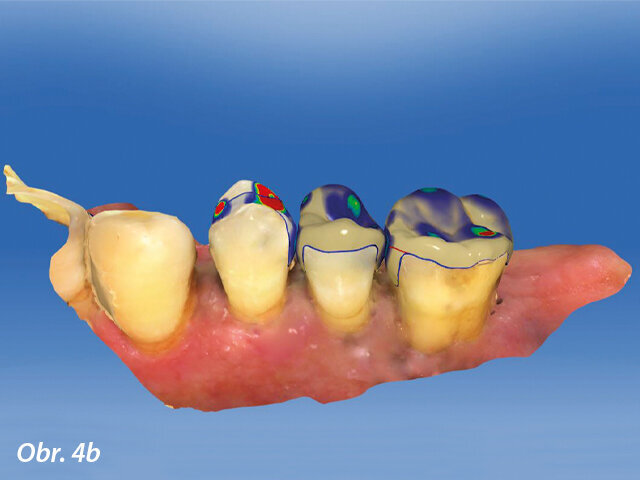

CAD výroba v dolní čelisti.